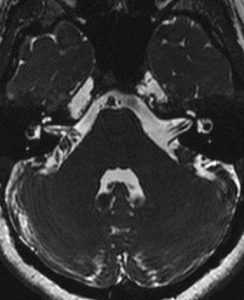

В норме мозжечок на МРТ головного мозга выглядит как неоднородное анатомическое образование, отделенное поперечной щелью. Контуры органа неровные: видны неглубокие борозды, которые делят на дольки боковые части (полушария) и центральную (червь). Размеры мозжечка в поперечном сечении достигают 9-10 см, в передне-заднем срезе - 4 см.

МРТ показывает миндалины мозжечка, расположенные на границе большого затылочного отверстия. У детей в возрасте 5-15 лет возможно каудальное смещение анатомического образования в позвоночный канал (в норме не более 5 мм).

Ядра мозжечка, представляющие скопление серого вещества в толще мозгового тела, на МРТ не определяются.